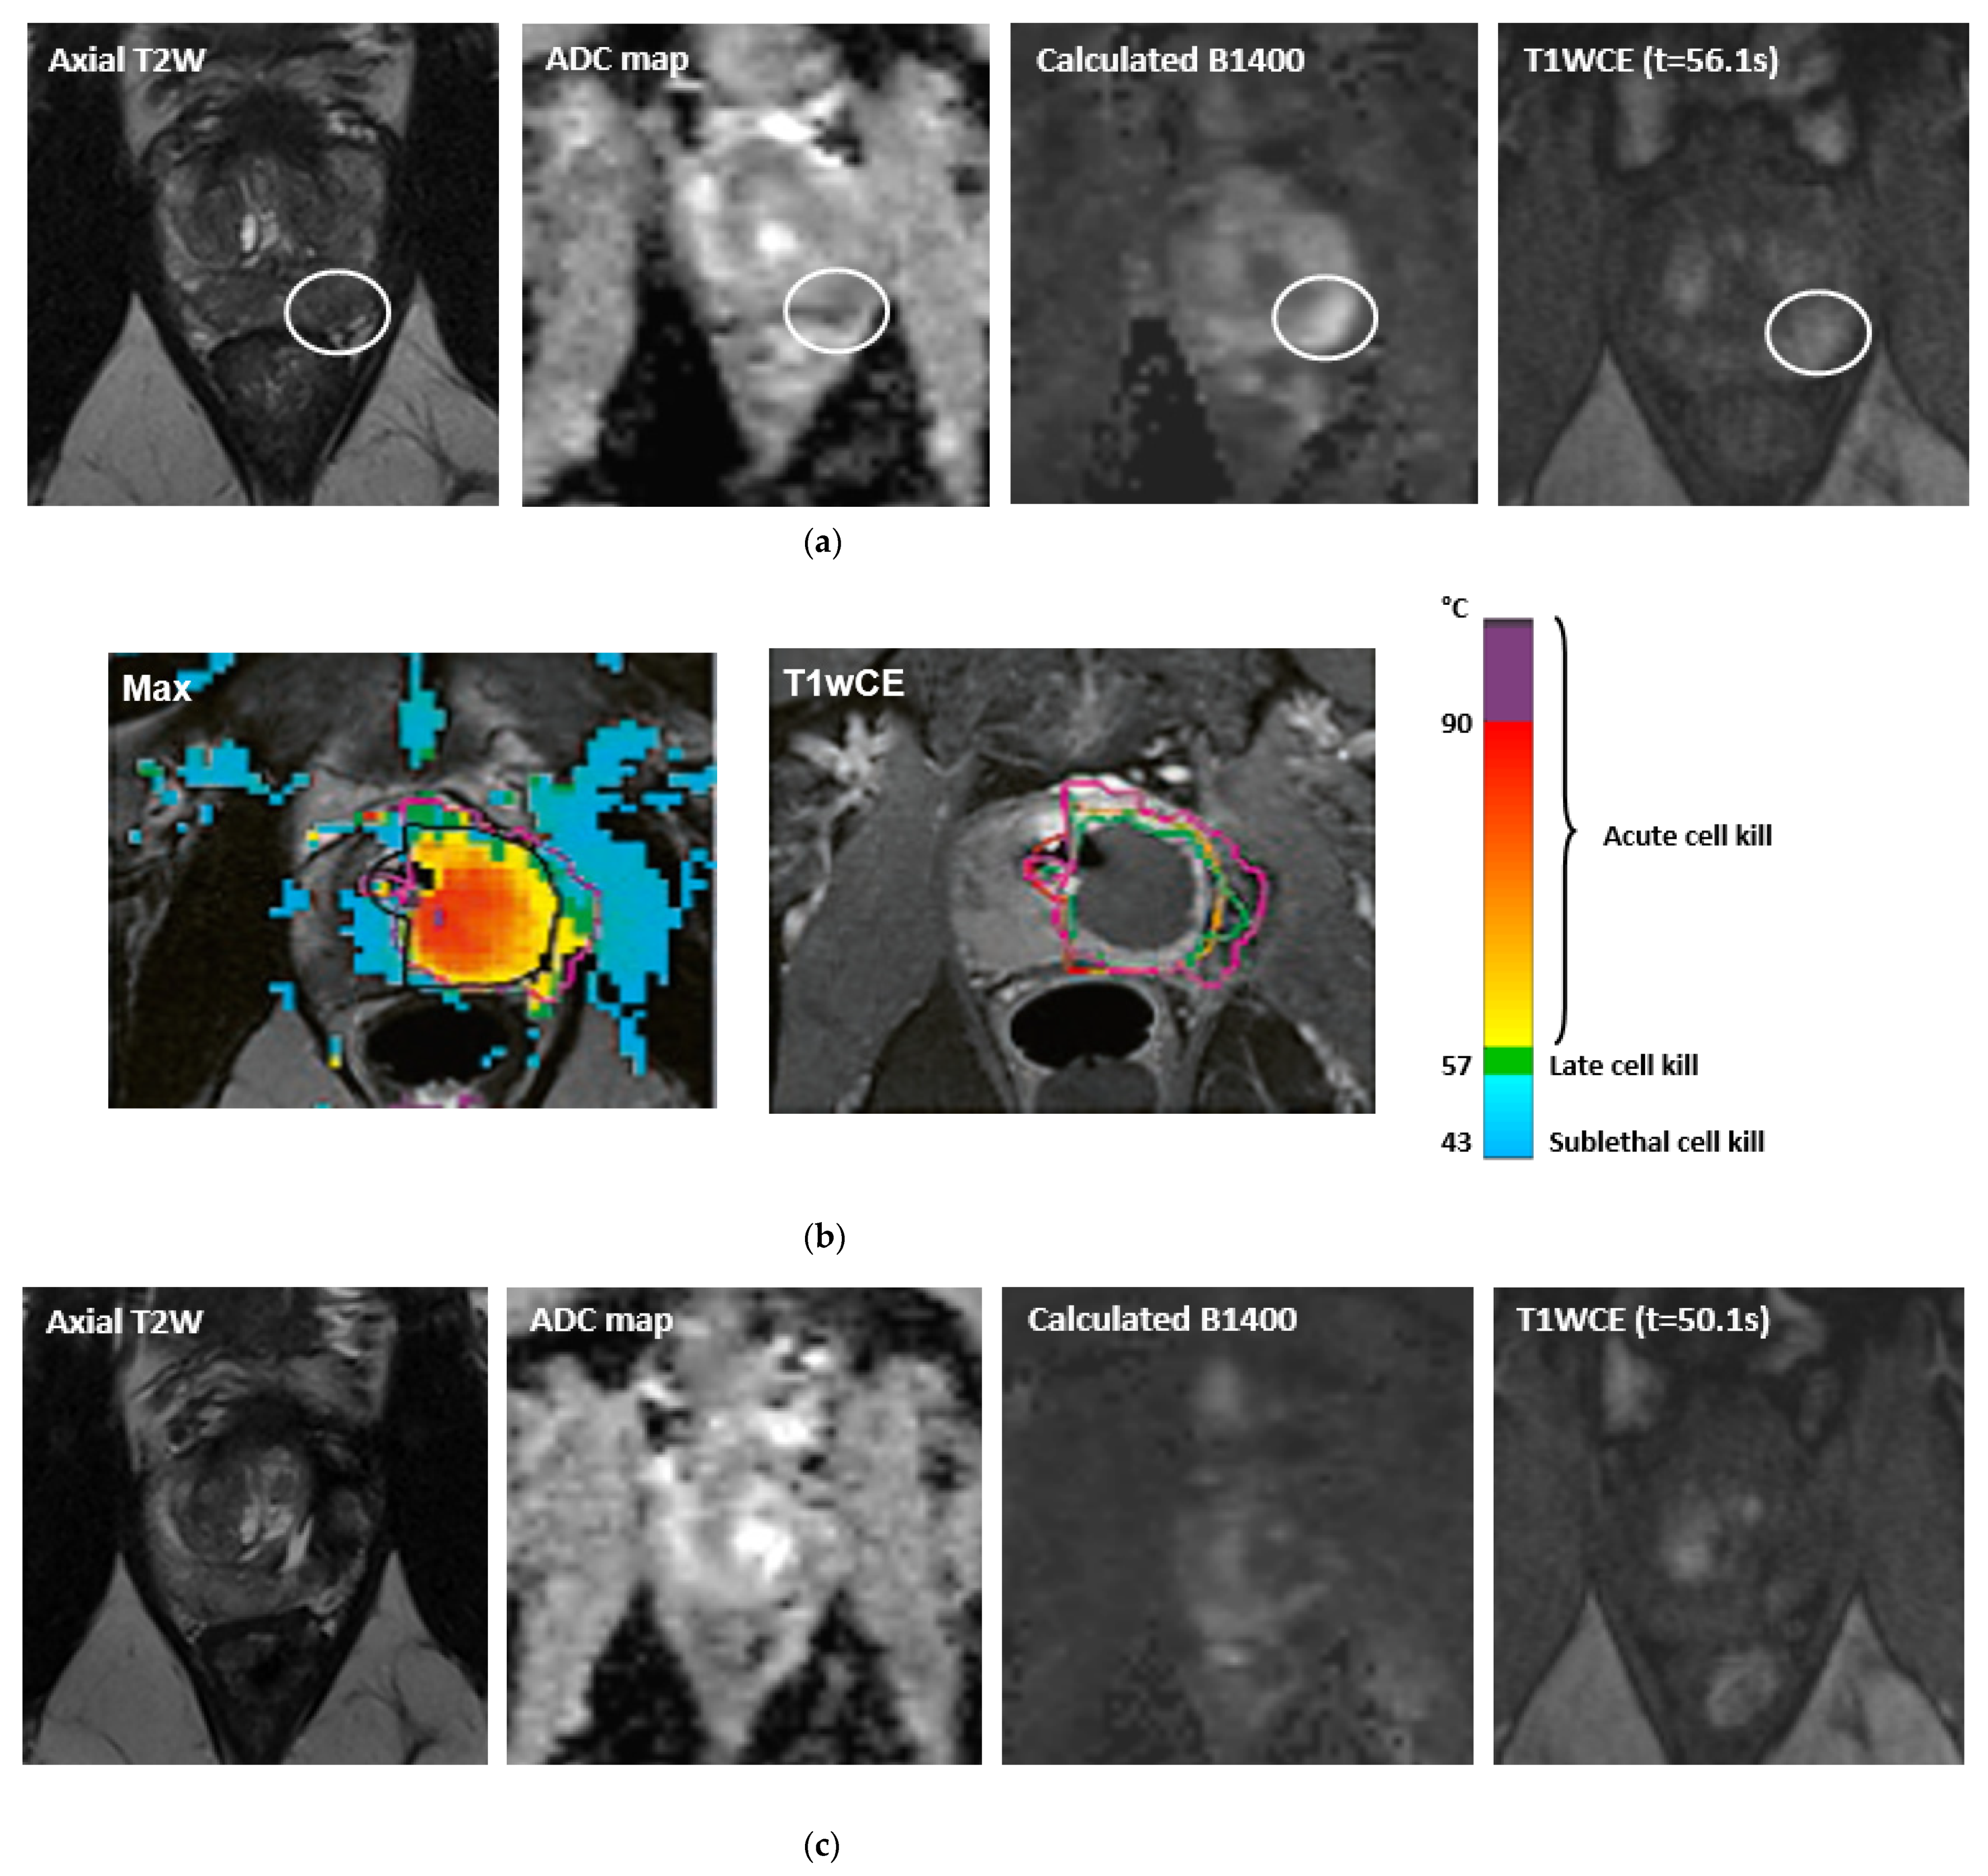

- Ghai, S.; Louis, A.S.; Van Vliet, M.; Lindner, U.; Haider, M.A.; Hlasny, E.; Spensieri, P.; Van Der Kwast, T.H.; McCluskey, S.A.; Kucharczyk, W.; et al. Real-Time MRI-Guided Focused Ultrasound for Focal Therapy of Locally Confined Low-Risk Prostate Cancer: Feasibility and Preliminary Outcomes. Am. J. Roentgenol. 2015, 205, W177–W184. [Google Scholar] [CrossRef]

- Ghai, S.; Perlis, N.; Lindner, U.; Hlasny, E.; Haider, M.A.; Finelli, A.; Zlotta, A.R.; Kulkarni, G.S.; Van Der Kwast, T.H.; McCluskey, S.A.; et al. Magnetic resonance guided focused high frequency ultrasound ablation for focal therapy in prostate cancer–phase 1 trial. Eur. Radiol. 2018, 28, 4281–4287. [Google Scholar] [CrossRef]

- Ghai, S.; Finelli, A.; Corr, K.; Chan, R.; Jokhu, S.; Li, X.; McCluskey, S.; Konukhova, A.; Hlasny, E.; van der Kwast, T.H.; et al. MRI-guided Focused Ultrasound Ablation for Localized Intermediate-Risk Prostate Cancer: Early Results of a Phase II Trial. Radiology 2021, 298, 695–703. [Google Scholar] [CrossRef]